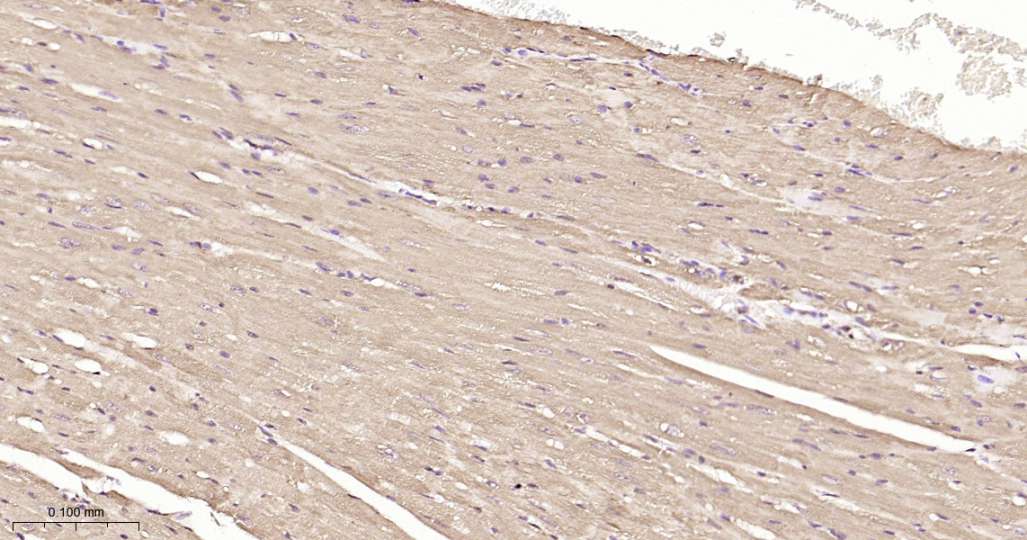

Immunohistochemical analysis of paraffin embedded Mouse heart tissue slide using IHC0591M (Mouse HSP90 beta Kit).